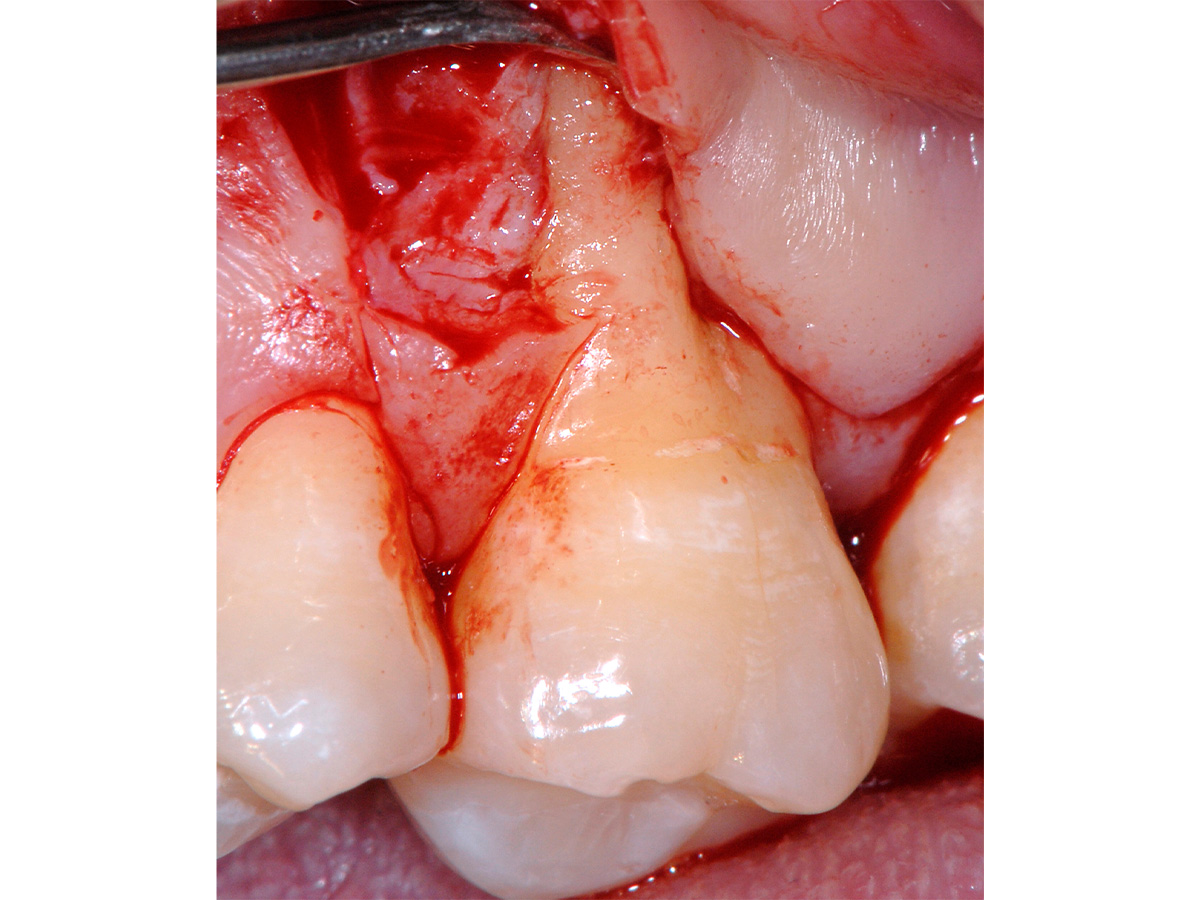

Abbildung 3

Mikrochirurgischer Zugang mit Schonung der interproximalen Bereiche. Vorbereitung dort durch Entepithelisierung zur späteren koronalen Verschiebung der bukkalen Lappenanteile.